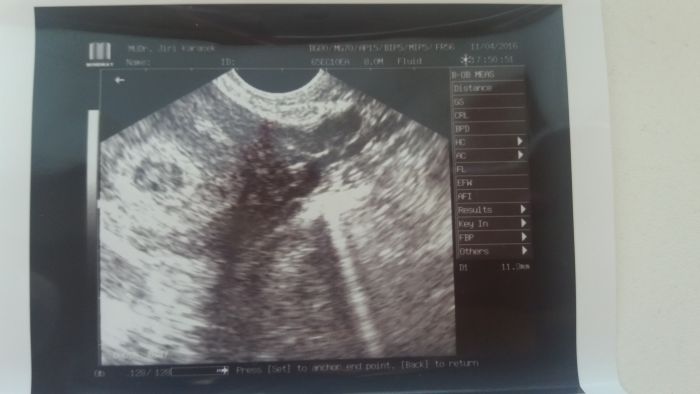

Na ultrazvuku váček celý šedý v 6. týdnu těhotenství

Ahoj maminky mám dotaz nemáte někdo s tímto zkušenost? Můj pan doktor mi řekl ze váček je celý šedý ale viděl srdeční akci a řekl mi at vydržím 14 dní :((

Asi jenom špatná kvalita zobrazení, možná nějaké rušení